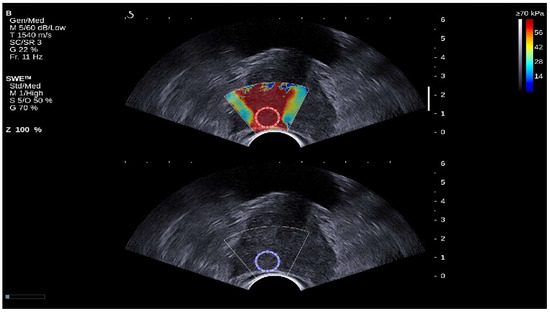

2.2. Image Reconstructions

Figure 1. SWE images with b-mode ultrasound image of prostate cancer lesion. At the top (Red circle), the ROI is selected from the SWE image, and it is duplicated automatically in the B-mode ultrasound image (Blue circle). The red color map in the SWE image correspond to areas of higher stiffness, whereas the blue color map indicate areas of lower stiffness.